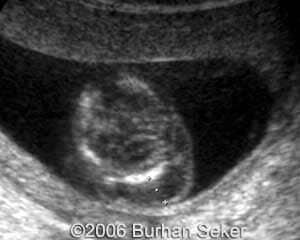

This a fetus with a cystic hygroma diagnosed at 13 weeks and 3 days. Karyotype was normal. The pregnancy was interrupted at 16 weeks.

At 16 weeks.Note the pleural effusion